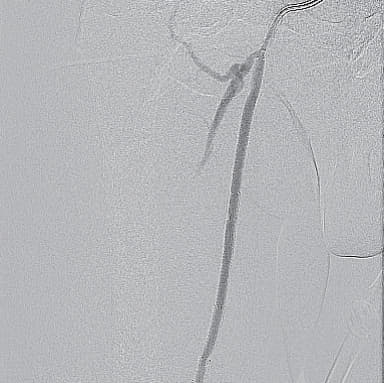

- マイクロカテーテルは硬化した閉塞部を通過せず、metal tip typeのマイクロカテーテルも通過しなかったことから、ブロッケンブロー針にて病変通過(図4)

- デバイス通過が容易となりIVUS評価後にハイプレッシャーバルーンにて前拡張を行った(遠位部塞栓予防のため閉塞遠位端はあえて前拡張せず)(図5)